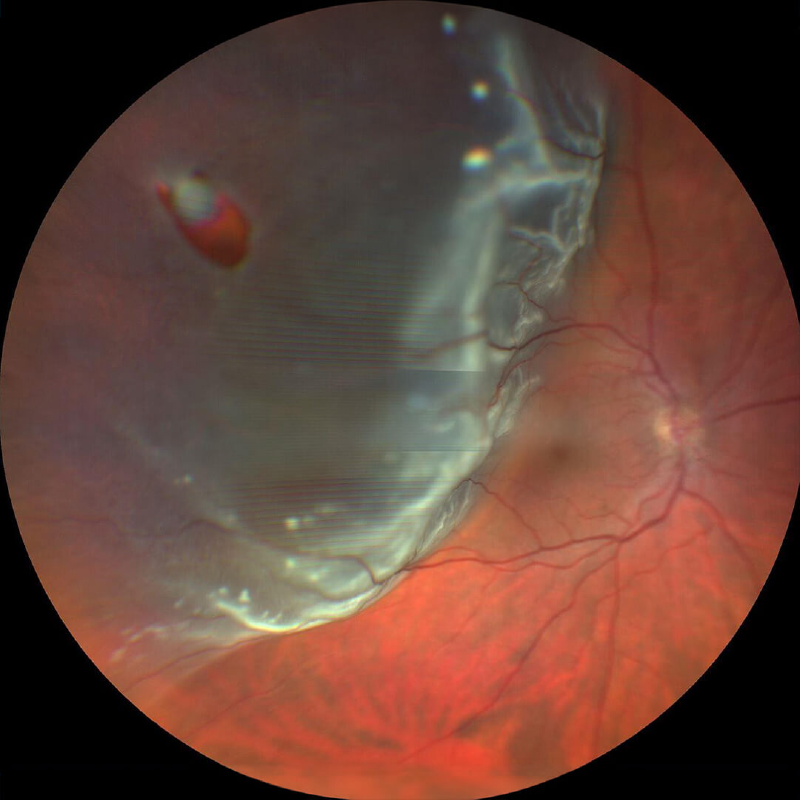

DESPRENDIMIENTO DE RETINA

DESPRENDIMIENTO DE RETINA

¿Que es el desprendimiento de retina?

DESPRENDIMIENTO DE RETINA

¿Qué es un desprendimiento de retina?

Un desprendimiento de retina es una afección ocular grave en la que la retina, la capa sensible a la luz en la parte posterior del ojo, se separa de la capa subyacente llamada epitelio pigmentario retiniano. Cuando esto sucede, la retina no puede funcionar correctamente y se produce una pérdida de visión.

¿Cuál es la causa de un desprendimiento de retina?

- Desgarro retiniano: Un desgarro o agujero en la retina puede permitir que el líquido se filtre debajo de ella y la separe del epitelio pigmentario.

- Traumatismo ocular: Un golpe o lesión en el ojo puede causar un desprendimiento de retina.

- Enfermedades oculares: La retinopatía diabética puede aumentar el riesgo de desprendimiento de retina.

- Cirugía ocular: En raras ocasiones, un desprendimiento de retina puede ocurrir después de una cirugía ocular.

¿Qué molestias produce un desprendimiento de retina?

- Destellos de luz: Los destellos de luz en el campo visual, especialmente en la visión periférica, pueden ser un signo de un desgarro retiniano, que puede preceder a un desprendimiento de retina.

- Moscas volantes: Las moscas volantes son pequeñas manchas o puntos que flotan en el campo visual. Si aparecen repentinamente o aumentan en número, pueden ser un signo de un desgarro retiniano.

- Visión borrosa: La visión borrosa, especialmente en la visión periférica, puede ser un signo de un desprendimiento de retina.

- Cortina o velo en el campo visual: La percepción de una cortina o velo que cae sobre el campo visual puede ser un signo de un desprendimiento de retina.

¿Cómo se diagnostica un desprendimiento de retina?

- Agudeza visual.

- Dilatación de las pupilas.

- Examen del fondo de ojo.

¿Cómo se trata un desprendimiento de retina?

- Fotocoagulación con láser: Se utiliza para sellar los desgarros retinianos y prevenir el desprendimiento de retina.

- Crioterapia: Se utiliza para congelar y sellar los desgarros retinianos.

- Cirugía: Existen diferentes tipos de cirugía para reparar un desprendimiento de retina, como la colocación de un cerclaje, la neumoretinopexia o la vitrectomía.

¿Cuáles son algunas recomendaciones para pacientes con desprendimiento de retina?

Es importante que las personas con síntomas de un desprendimiento de retina consulten con un oftalmólogo de inmediato.